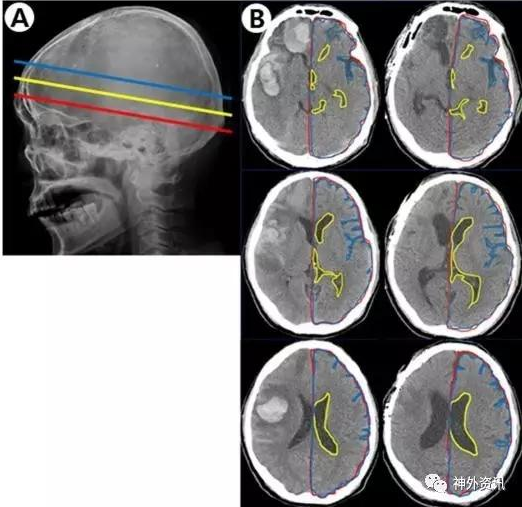

該研究收集作者所在單位2011年至2015年接受手術(shù)治療的自發(fā)性腦出血患者。研究對(duì)象的血腫位于幕上單側(cè)大腦半球;根據(jù)術(shù)前和術(shù)后3個(gè)月在頭顱CT軸位3個(gè)平面,即室間孔平面、透明隔平面和側(cè)腦室平面上的影像片(圖1)

計(jì)算發(fā)生出血對(duì)側(cè)的腦實(shí)質(zhì)面積與同側(cè)顱腔面積之比以消除個(gè)體差異,分析與對(duì)側(cè)腦組織體積變化的相關(guān)因素。

總共納入44例患者,其中12例血腫清除后骨瓣復(fù)位,15例行血腫清除加去骨瓣減壓術(shù),17例行血腫穿刺引流術(shù)。結(jié)果表明,所有患者術(shù)前與術(shù)后3個(gè)月CT圖像上,在室間孔、透明隔和側(cè)腦室3個(gè)平面的對(duì)側(cè)腦組織與同側(cè)顱腔面積平均比值,分別為92.3%比88.8%、90.3%比85.3%和86.9%比82.5%,差異均有統(tǒng)計(jì)學(xué)意義(P<0.001)。血腫破入腦室是導(dǎo)致對(duì)側(cè)腦組織體積縮小的最顯著因素(P=0.006);此外,入院時(shí)GCS評(píng)分低(P=0.016)和吸煙(0.039)也是對(duì)側(cè)腦組織體積縮小的獨(dú)立影響因素。